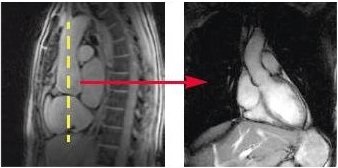

- Prescribe and acquire a sagittal localizer.

- Prescribe and acquire coronal slices (yellow line indicates graphic location) for an ascending aorta view.

Figure 1. Coronal slice location